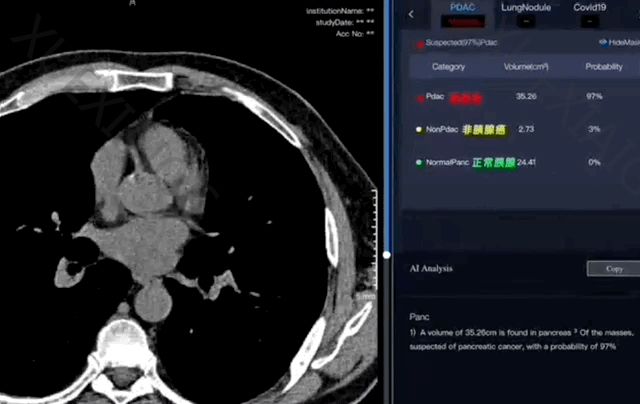

世界前沿的医学研究成果,PANDA模型,通过结合平扫CT和AI技术,能够准确识别早期胰腺癌病变。这一成果在国际医学顶级期刊Nature Medicine上发表,仅用3个月时间就在浙江丽水的两家医院中得到了实际应用,标志着从理论到实践的快速转化。

胰腺癌的早期筛查对于提高患者的生存率至关重要。胰腺癌被称为“癌王”,早期很难被发现,而PANDA模型的应用大大提高了早期诊断的准确性。这一模型经过广泛的临床验证,显示出比人工诊断高出34.1%的敏感性,为胰腺癌等疾病的早期发现和治疗提供了新的可能。